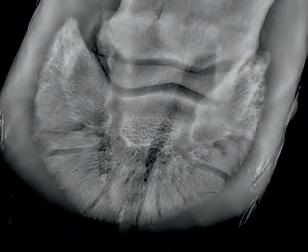

Radiographic proof in clinical results

BONE Gold nutritional bone joint and collagen supplement was formulated to provide some of the essential amino acid requirements of collagen type I, II and III (found in bone and connective tissue) in addition to supporting the nitric oxide pathway which has been found to assist in the formation of bone callus postinjury.

Veterinary surgeons have recommended that Bone Gold may assist with sore shins, tendon injuries, ligament injuries, osteoarthritis and post-surgery in horses and polyarthritis, geriatric osteoarthritis, and post-surgery in dogs.

Here is a veterinary radiographic report on a horse with a fracture evident on the medial toe and after treatment and feeding Bone Gold during this period. More information on these products can be found at www.vetgold.com.au

VETERINARY RADIOGRAPHIC REPORT

HORSE: "XXXXXXXX"

DATES OF EXAMINATION: 26TH AUG, 21ST OCT 21 & 17TH NOV '21

PLACE: XXXXXXXXXX FARM

XXXXXXX's left and right front feet were radiographed on 26th Aug, 21st Oct (8 weeks) and again on the 17th Nov '21(12 weeks).

RADIOGRAPHS:

26.08.21: Right Front: Large P3 solar margin fracture evident on medial toe 32.6mm x 4.1mm with approximately 1.4mm separation from parent bone as below left image.

21.10.21: Right Front: Fine residual 4.2mm fracture still evident, approximately 90% resolution

17.11.21: Right Front: Fracture fully resolved

RECOMMENDATIONS:

Radiographic results as of the 17th Nov '21 show total resolution of the original fracture.

XXXXXXX was reshod today utilising off an alloy shoe with a toe clip - inner circumference seated out to avoid any sole pressure.

The horse can return to training. Please do not hesitate to contact me if you have any further queries

COMMENTS:

Solar margin Type IV fractures of this magnitude have well-documented internationally published healing rates of 7 - 12 months. Full resolution of these fractures is rare as most often the fracture fragments are resorbed.

Full resolution in a 3 month period was not anticipated.

The horse was on Bone Gold 3 x scoops fed once per day for this period.

"Go to our webpage or scan the QR Code to see more Bone Gold Radiographic results"